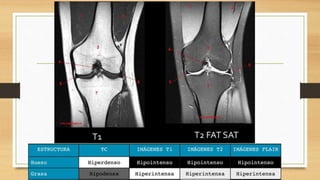

EXAMENES AUXILIARES

EXAMENES AUXILIARES Linea deBlumenssat, cicatriz del cartílago hialino